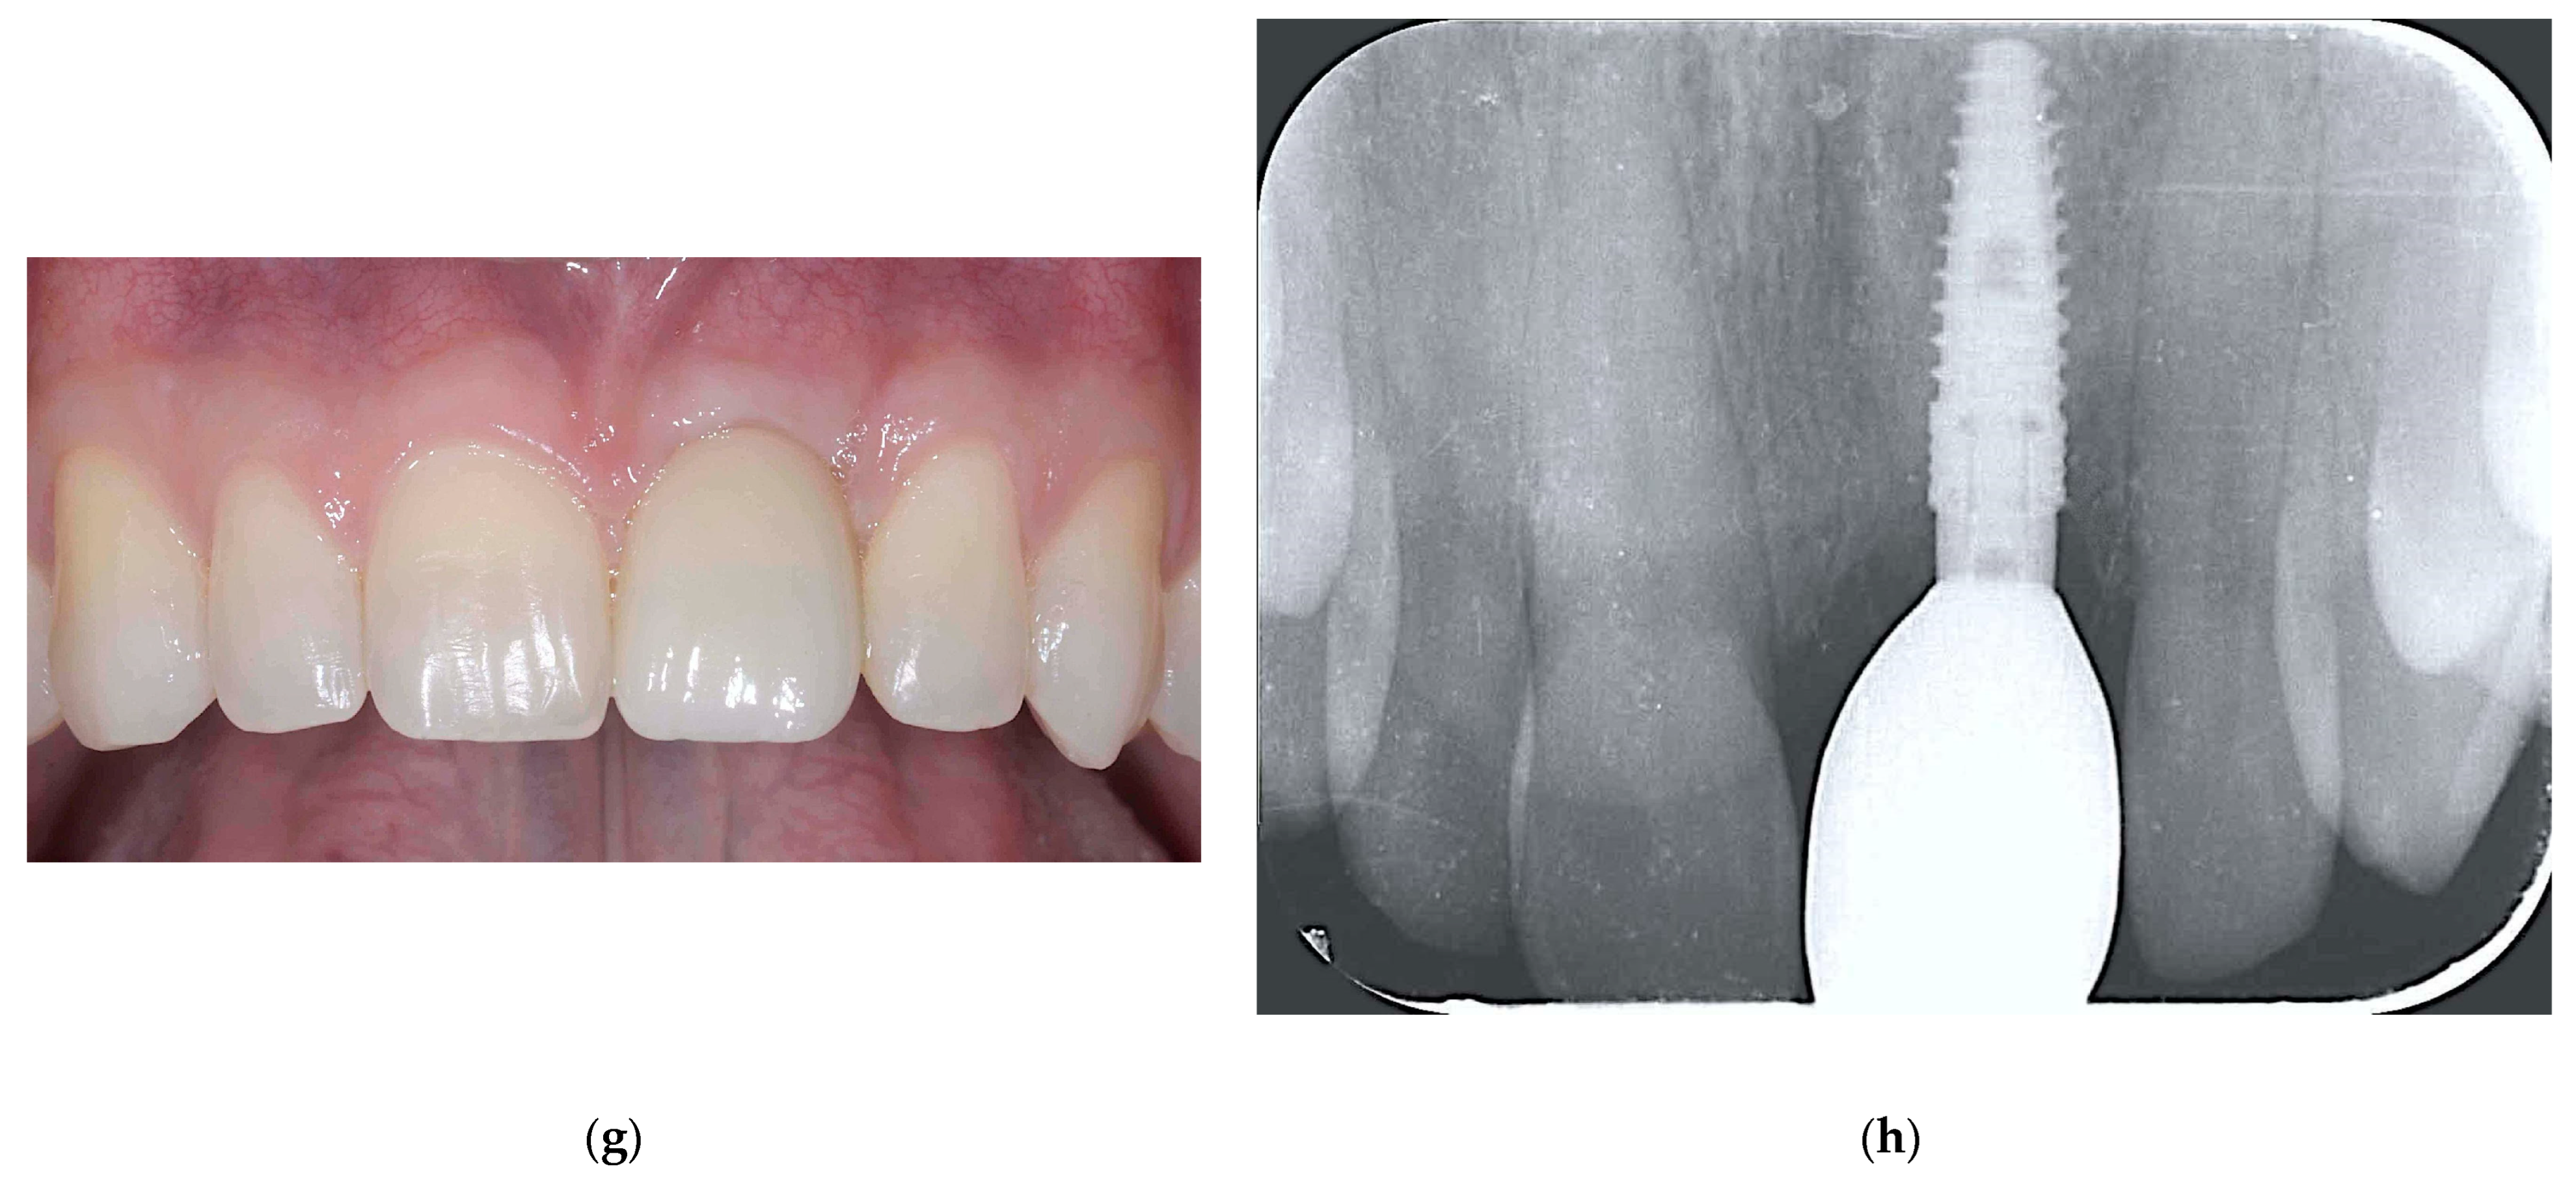

2.2.3. ARP and Delayed Implant Placement Using F.I.R.S.T.

- Foti, V.; Rossi, R. Fibrinogen-induced regeneration sealing technique (first) an improvement and modification of traditional gbr: A report of two cases. Mod. Res. Dent. 2020, 5, 476–485. [Google Scholar]

- Foti, V.; Savio, D.; Rossi, R. One-time cortical lamina: A new technique for horizontal ridge augmentation. A Case Ser. Br. J. Healthc. Med. Res. 2021, 8, 22–30. [Google Scholar] [CrossRef]

- Foti, V. Fibrinogen-induced regeneration sealing technique (f.I.R.S.T.). In Building Better Bone: A Comprehensive Guide to gbr Techniques; Rossi, R., Ed.; Quintessence Publishing: Batavia, IL, USA, 2024; pp. 210–227. [Google Scholar]

- Faro, L.L.; Strappa, E.M.; Carù, F.G.; Nanni, M.; Invernizzi, M.; Testori, T. Rigenerazione ossea guidata con tecnica first (fibrin-induced regeneration sealing technique). Case report con evidenze istologiche. Quintessenza Internazionale Riv. Di Odontoiatr. 2023, 37, 10–21. [Google Scholar]